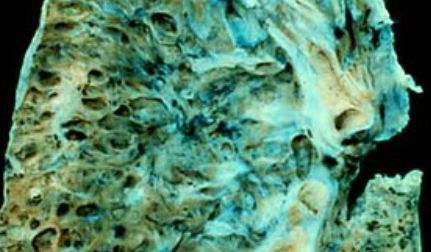

폐섬유증은 폐 조직이 점차 굳어지면서 호흡장애를 일으키는 질환인데요. 폐섬유화증은 폐섬유증의 한 종류로, 폐 조직이 딱딱해지는 현상을 의미합니다. 이러한 변화는 폐에 염증이 생겼다가 아무는 것이 반복되면서 마치 상처가 굳은살과 흉터를 만드는 것과 비슷한데요.

폐섬유증과 폐섬유화증의 주요 원인은 다양합니다. 그러나 가장 흔한 원인 중 하나는 만성 염증입니다. 만성 염증은 폐 조직에 지속적인 염증 반응을 유발하며, 이는 폐 조직의 손상과 염증 반응이 반복되면서 섬유화 과정을 유발합니다. 이 과정에서 폐 조직 내 결합조직이 비정상적으로 증식하고 딱딱하게 굳어지는 현상이 나타나게 됩니다.

폐섬유증과 폐섬유화증은 호흡곤란, 저산소증, 심근경색증 등의 심장질환과의 연관성이 있습니다. 또한, 폐렴, 폐색전증, 폐암 등의 합병증이 발생할 수 있으며, 이로 인해 사망 위험이 높아집니다. 폐섬유증과 폐섬유화증은 호흡기 질환으로서, 치료와 관리가 중요하며 합병증의 예방과 조기 발견이 필요합니다.